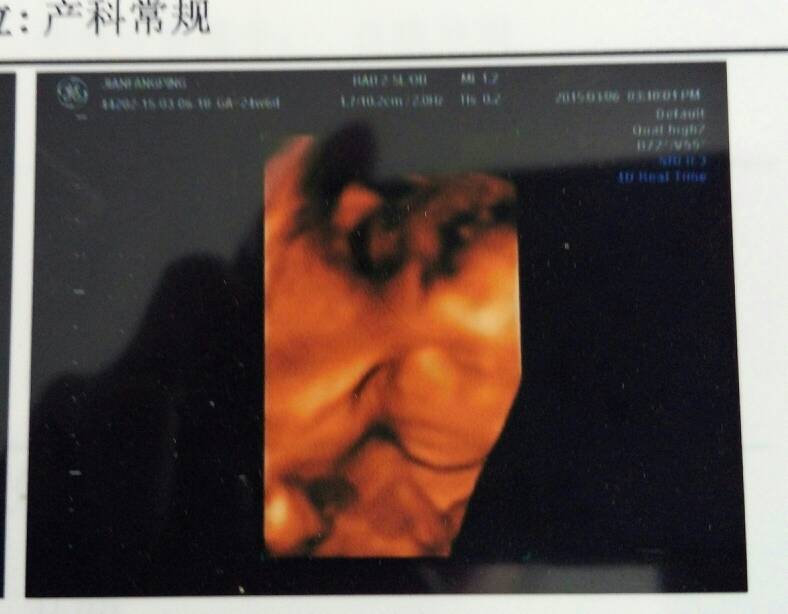

我家宝贝,大家觉得是贝勒还是格格呢 我家宝贝,大家觉得是贝勒还是格格呢😍 点击展开 ^O^回忆 2015-04-03 15:41 为您推荐: 其他回答 男孩第一感觉 少年*娃@ 2015-04-03 16:53 你觉得呢, 阳光味道_VPxD 2015-04-03 16:31 看不懂。。 雯欢乐的妈 2015-04-03 16:30 祝宝妈好孕 ♀_aDOI 2015-04-03 16:05 看不懂。。 少靓舒晴 2015-04-03 15:55 加载更多 相关问题 我家宝贝80天了怎么笑还不是格格格格笑呢?请问怎么回事?什么时间给会呢? 宝贝笑的超萌